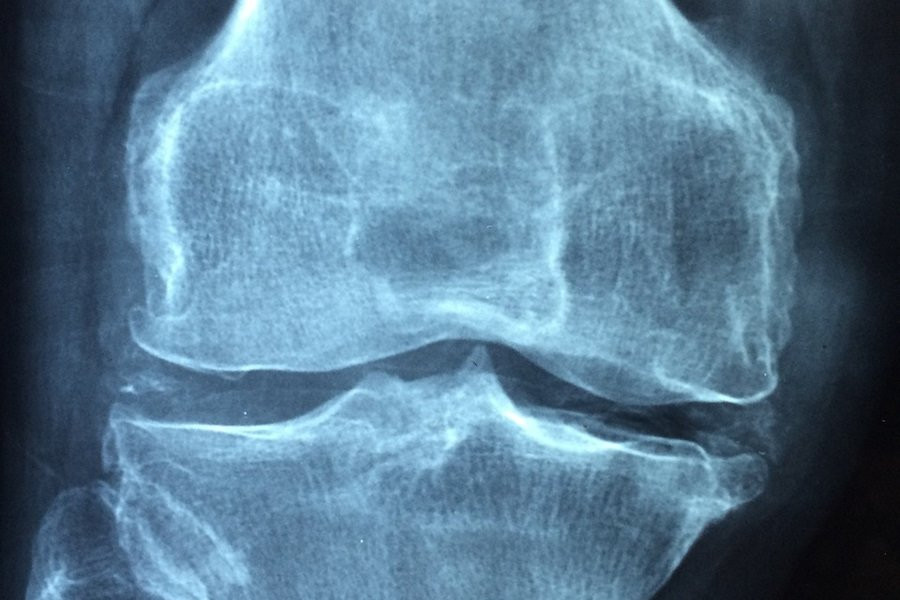

Учёные США нашли бактерии, при ревматоидном артрите атакующие хрящевую ткань

Ученые заметили, что у пациентов с серьезными формами ревматоидного артрита в их кишечнике обнаруживается большое количество бактерий Eggerthella lenta. Эти бактерии изменяют обмен веществ в организме и стимулируют активность иммунных клеток, ответственных за производство антител, которые атакуют собственные ткани организма. Это приводит к ухудшению состояния больных и усилению боли.